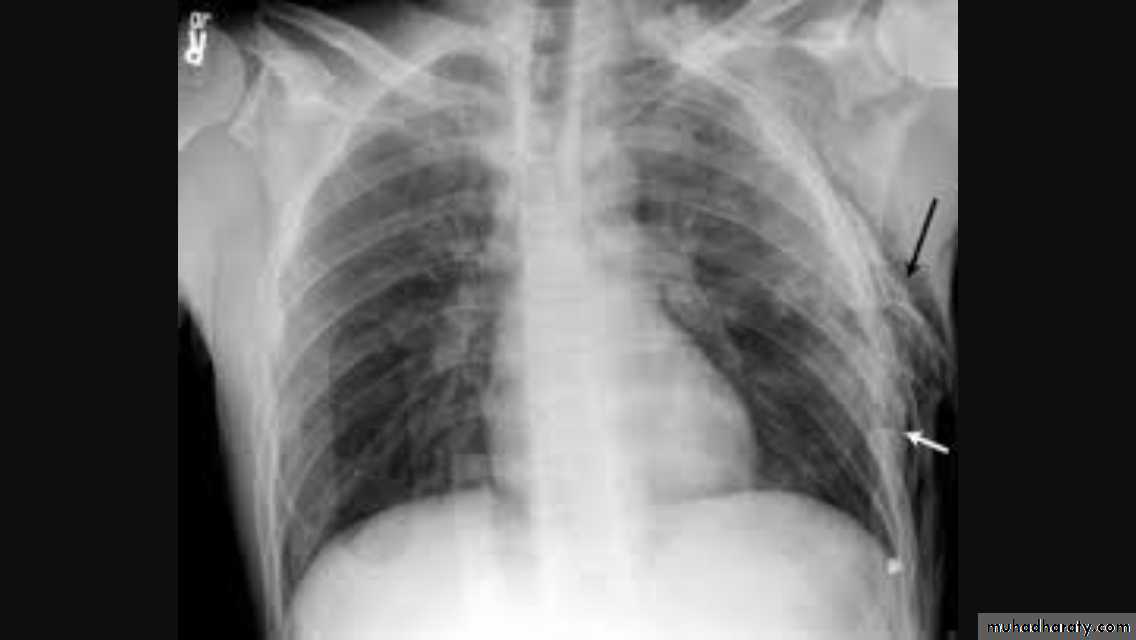

• Pleural effusion : collection of fluid within the pleural space. This can be further divided into Transudate , exudate, according to protein content .Other type of fluid collection within pleural space are

• Chest x-rays are the most commonly used examination to assess for presence of a pleural effusion, however it should be noted that on a routine erect frontal chest x-ray as much as 200-500 ml of fluid is

• required before it becomes evident .

blunting of the costophrenic angle

blunting of the cardiophrenic angle

fluid within the horizontal or oblique fissures

eventually a meniscus will be seen, on frontal films seen laterally and gently sloping medially

with large volume effusions, mediastinal shift occurs away from the effusion

• Lateral films are able to identify a smaller amount of fluid ( about75%)as the costophrenic angles are deepest posteriorly posteriorly

Pleura effusion signs

Obliteration of costo-pherinic anglesMeniscus sign

Lenticular sign